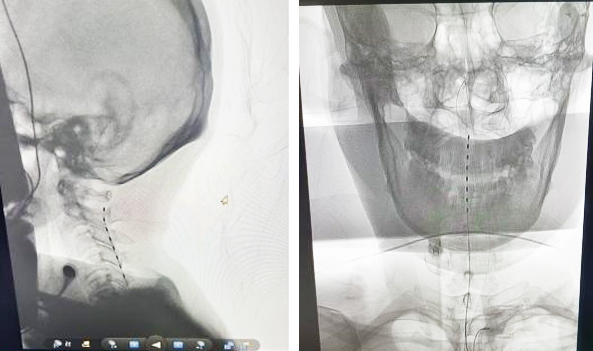

經(jīng)過充分術(shù)前準(zhǔn)備評估后,在介入室、手術(shù)室、麻醉科、器械科通力合作下,郝懷勇、葉翔、關(guān)家文醫(yī)生和介入室盧慶林主任,完成了我院第二例高頸髓脊髓電刺激促醒術(shù)。該患者開機(jī)第三天在沒有拔除氣管切開管的情況下,已經(jīng)能夠說出自己名字,并能夠進(jìn)行短暫的語言交流,目前正在進(jìn)一步康復(fù)中。